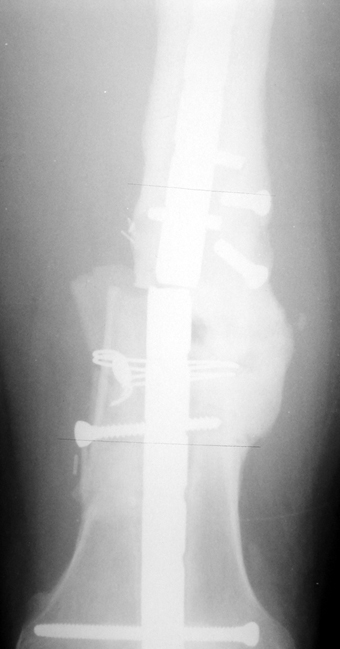

Vaka 2